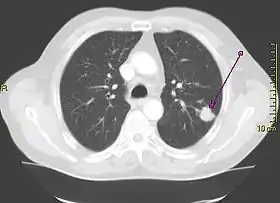

A "lung window" CT scan showing a lung cancer in the left lung

Contrast agents are sometimes used in CT scans of the chest to accentuate or enhance the differences in radiopacity between vascularized and less vascularized structures, but a standard chest CT scan is usually non-contrasted (i.e. "plain") and relies on different algorithms to produce various series of digitalized images known as view or "window". Modern detail-oriented scans such as high-resolution computed tomography (HRCT) is the gold standard in respiratory medicine and thoracic surgery for investigating disorders of the lung parenchyma (alveoli).

Contrasted CT scans of the chest are usually used to confirm diagnosis of for lung cancer and abscesses, as well as to assess lymph node status at the hila and the mediastinum. CT pulmonary angiogram, which uses time-matched ("phased") protocols to assess the lung perfusion and the patency of great arteries and veins, particularly to look for pulmonary embolism.[1]